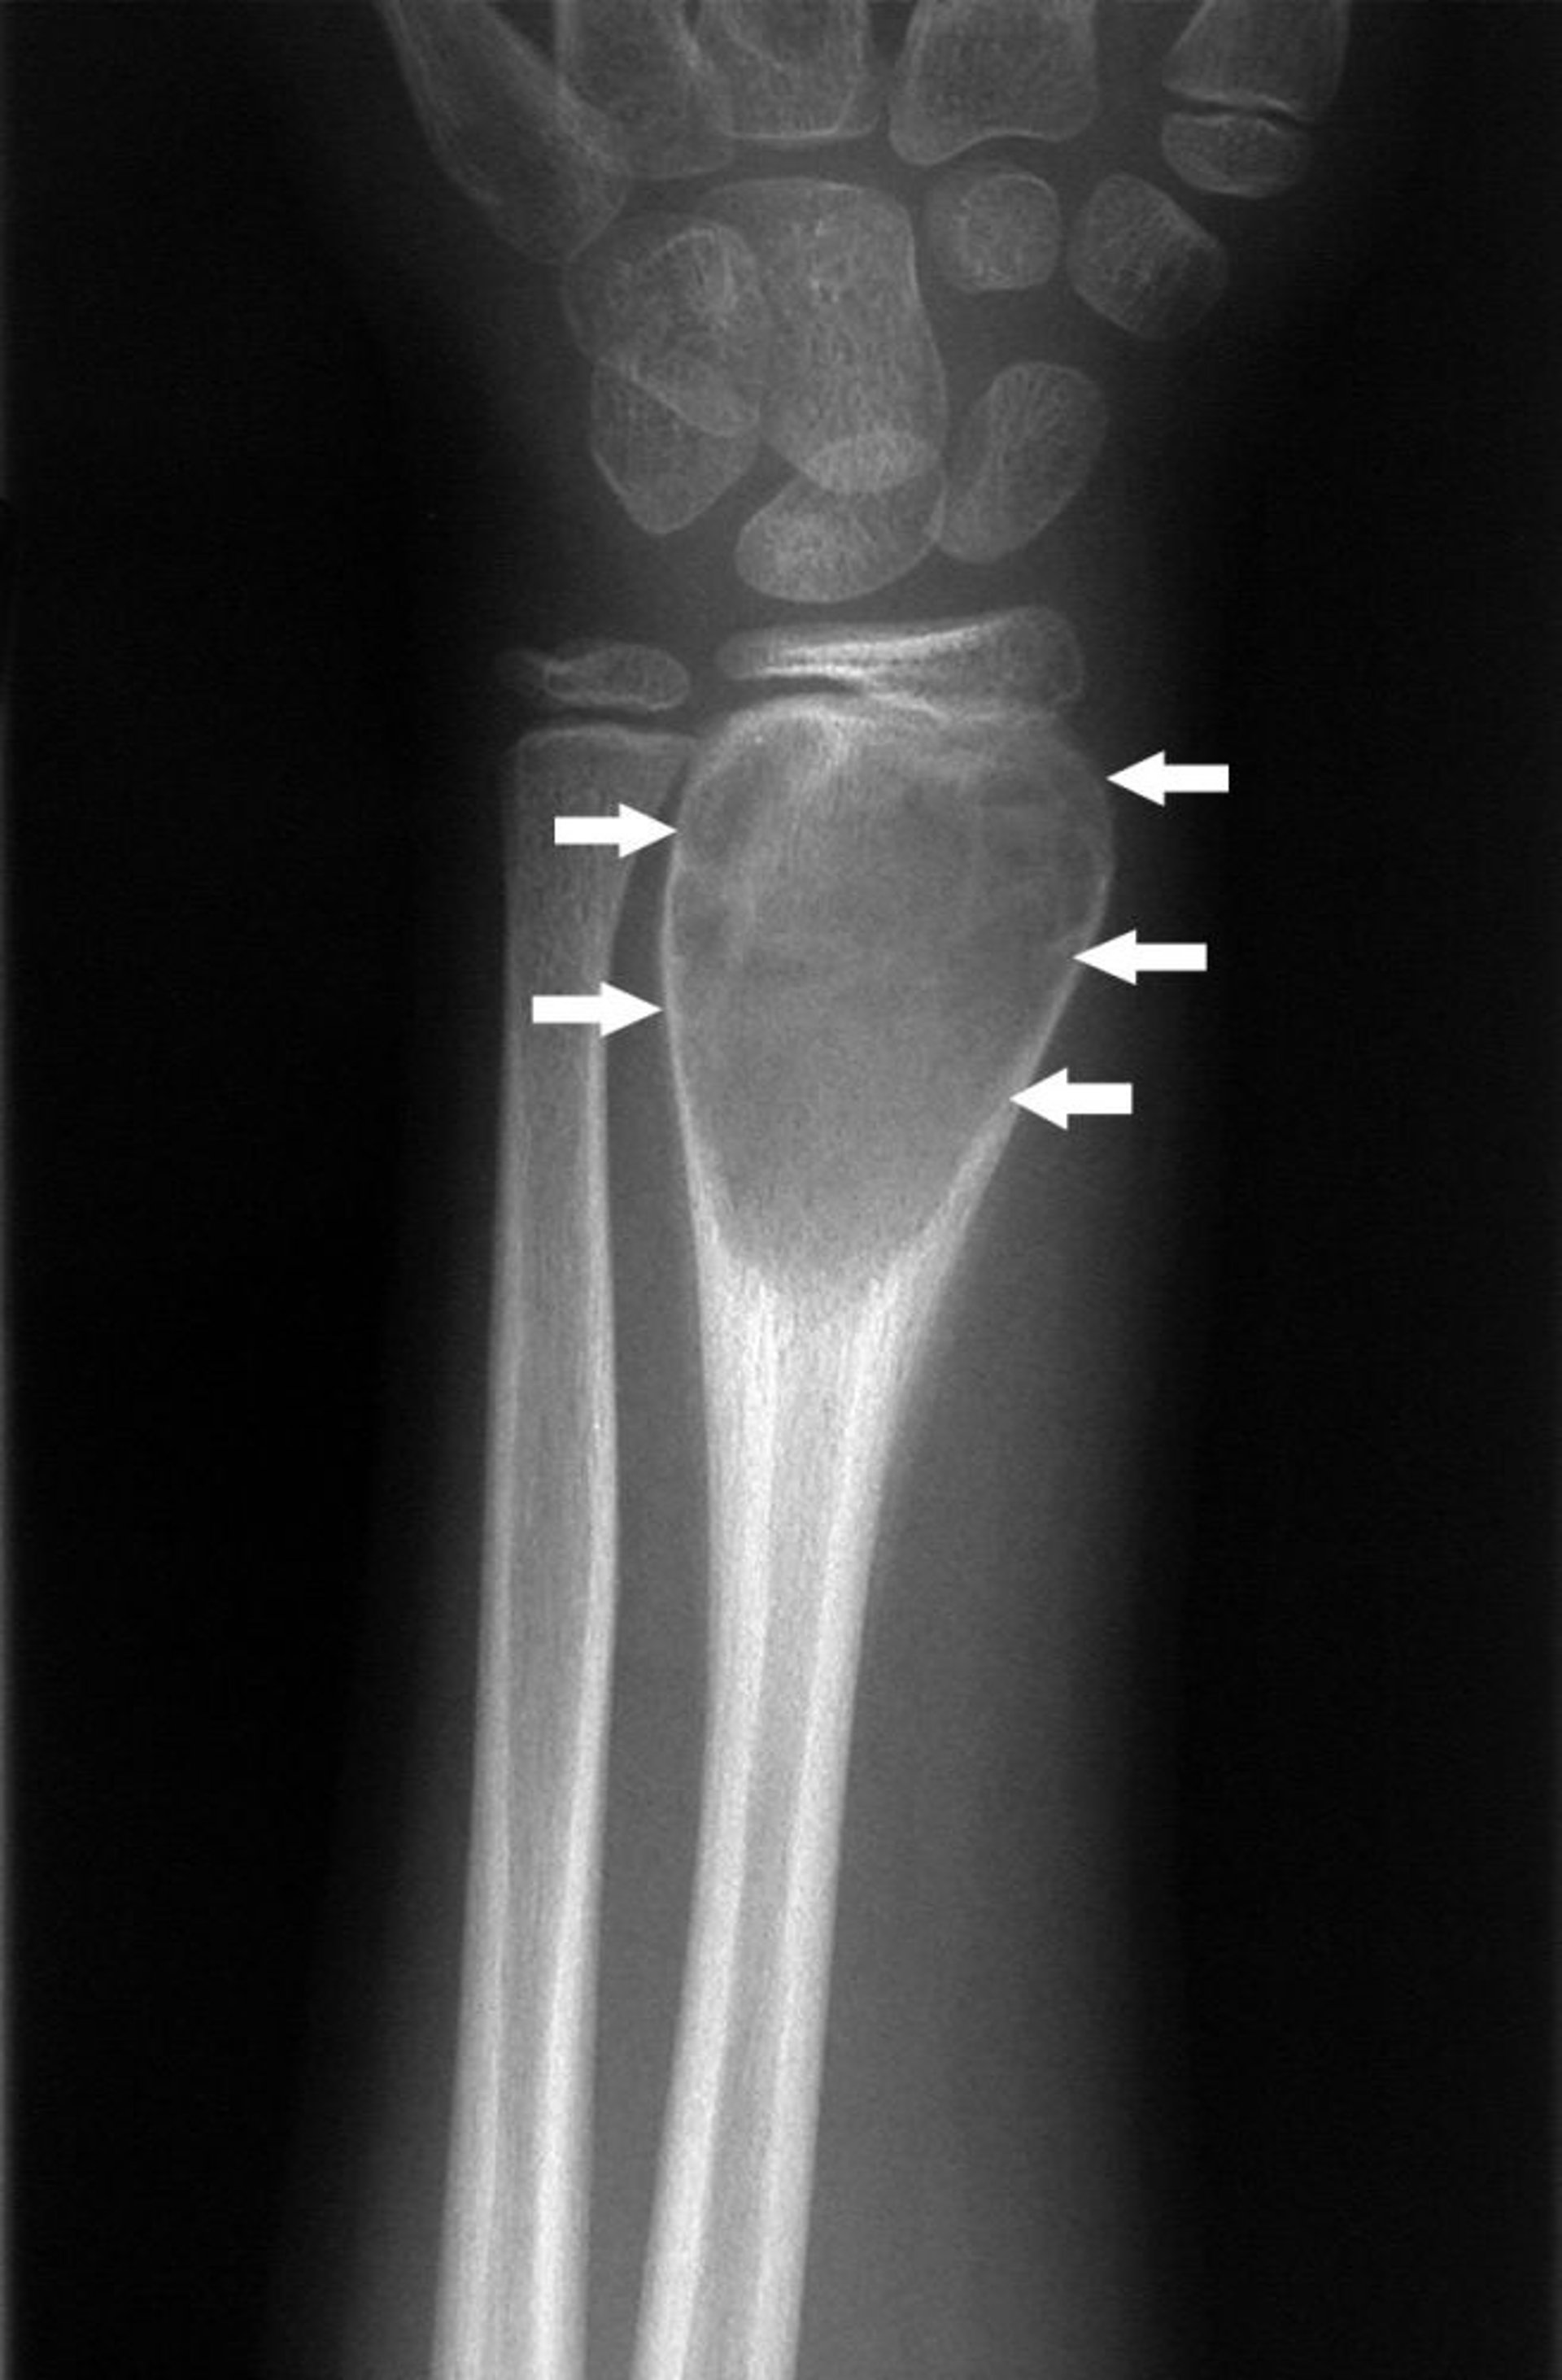

Radiographie du poignet

Cette radiographie du poignet montre un kyste osseux qui entraîne une hypertrophie de l’extrémité de l’os (flèches).

Image publiée avec l’aimable autorisation des Drs Michael J. Joyce et Hakan Ilaslan.